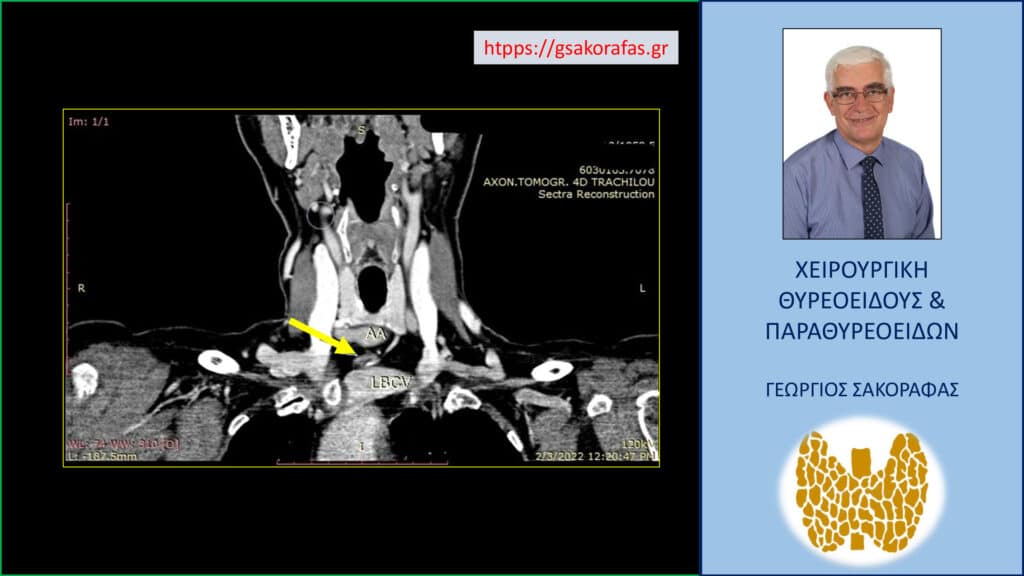

Ο απεικονιστικός έλεγχος περιλαμβάνει κατά βάση το υπερηχογράφημα τραχήλου και την αξονική/μαγνητική τομογραφία. Η αρχική απεικονιστική εξέταση είναι το υπερηχογράφημα, στο οποίο παρατηρείται μάζα με ασαφή όρια, συνήθως στην ανατομική θέση ενός παραθυρεοειδούς αδένα. Η μάζα αυτή μπορεί να επεκτείνεται και στα γύρω όργανα και να τα διηθεί.

Μπορεί να παρατηρηθούν και παθολογικοί τραχηλικοί λεμφαδένες λόγω της ύπαρξης μεταστάσεων σε αυτούς. Η αξονική / μαγνητική τομογραφία είναι ιδιαίτερα χρήσιμη προκειμένου να αξιολογηθεί πριν την επέμβαση η ύπαρξη διήθησης (και η έκτασή της, αν υπάρχει) βασικών ανατομικών στοιχείων του τραχήλου από τον καρκίνο (όπως είναι η καρωτίδα αρτηρία, η τραχεία, ο λάρυγγας κλπ.).